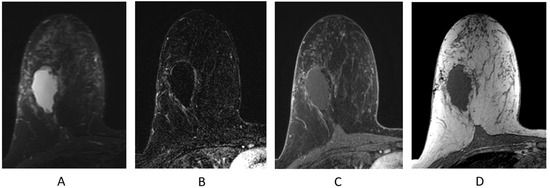

2.4.2. Mass (Figure 7B)